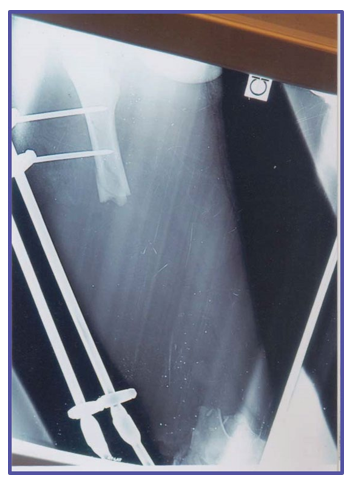

1. 35-year-old male with infected non-union fracture; interlocking nail and Gentamicin beads in place.

2. Close-up view of Gentamicin beads used in femur

3. Radiographic view of infected non-union with interlocking nail in situ and Gentamicin beads.